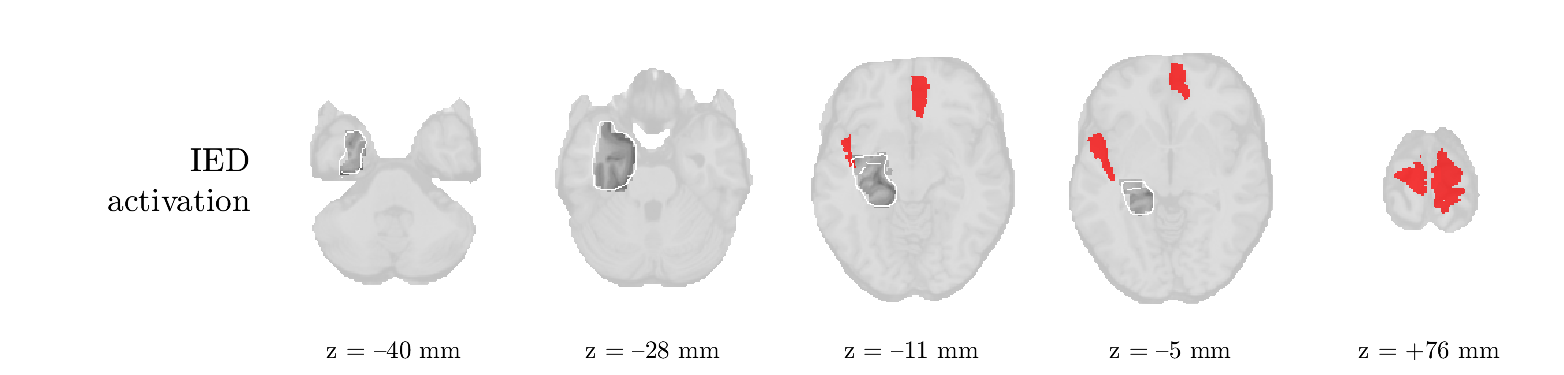

Patient 2

We analyze the solution with sources, and show the results in Figure 3 and 4. As for patient 1, we found a source which is strongly correlated to the MWF envelope, and which had a mostly low-frequency behavior characteristic for spikes. The topography is mostly uninformative, and does not clearly correspond to the patient’s clinical data. The third source is mostly present at both sides of the head, is very sparsely active in time, and has a high-frequency content: this is most likely an artifact due to the neck muscles. Again, there is one of the highest-entropy HRFs which belongs to a ROI in the IOZ. Now, the waveform is clearly resolved from the other HRFs, through the strong initial dip (before 0 seconds). Such a dip is sometimes observed in HRFs, but its underlying physiological mechanism is not yet fully understood. It is possible that this dip reflects altered vascular autoregulation near the IOZ (cfr. the explanation in the Section 1 of the main text), or a rapid depletion in oxygen due to IED generation (before the IED becomes visible on the EEG). Figure 4 furthermore shows that the IED-related component is significantly active in parts of the IOZ, and deactive in others. As mentioned earlier, this deactivation may or may not be due to errors in sign correction. Interestingly, the ROI with the high alteration in neurovascular coupling is distinct from both the activated and deactivated ROIs.